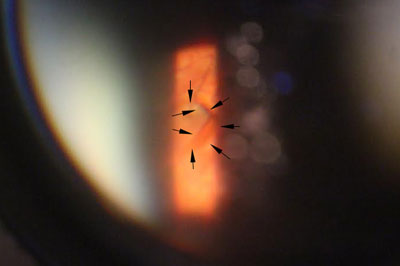

年屆四十至五十歲的病人,出現急症飛蚊大多是由於玻璃體液化以至出現「後玻璃體脫落」,當玻璃體從視神經盤脫離時,往往便出現較大和明顯的玻璃體「殘留物」,而導致嚴重飛蚊症狀,小部份病人亦會出現視網膜裂痕,出血和脫落等併發症,以致危害視力。雖然大部份病人沒有視力嚴重受損的風險,但較嚴重的飛蚊症狀會帶來視覺上的不便。治療此類飛蚊症,一般藥物治療效果有限,而侵入性外科手術 (玻璃體切除) 亦只適合如玻璃體出現嚴重出血或撕裂等併發症患者。

隨著激光技術的發展,近年已發展出激光治療飛蚊症,用於把較大和集中的玻璃體浮游物打散,以達到改善和消除飛蚊症狀,過程約十五至二十分鐘,沒有痛楚,並可於局部麻醉下進行。但並不是所有患有飛蚊症的人均適合做激光治療,如「飛蚊」物質較鬆散或位置太接近黃斑或晶體,便不適合進行此類激光治療,以免導致白內障或黃斑受損等併發症。